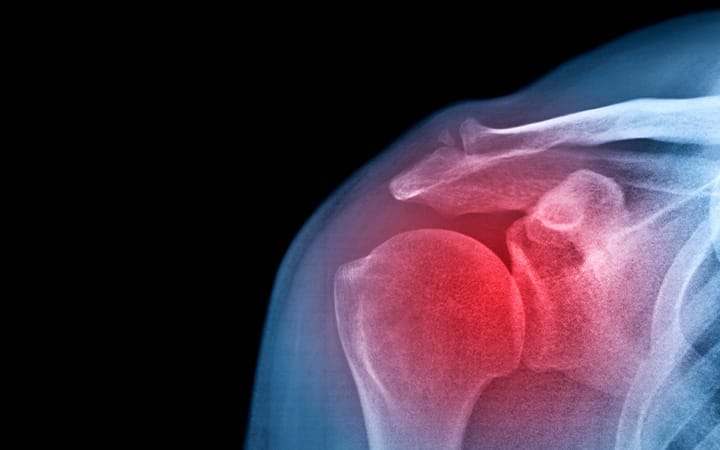

Frozen shoulder, medically known as adhesive capsulitis, is an inflammation of the lining of the shoulder joint. When the joint becomes inflamed and thickens, the typical range of motion of the shoulder becomes limited.

The result? A stiff shoulder that becomes increasingly painful.